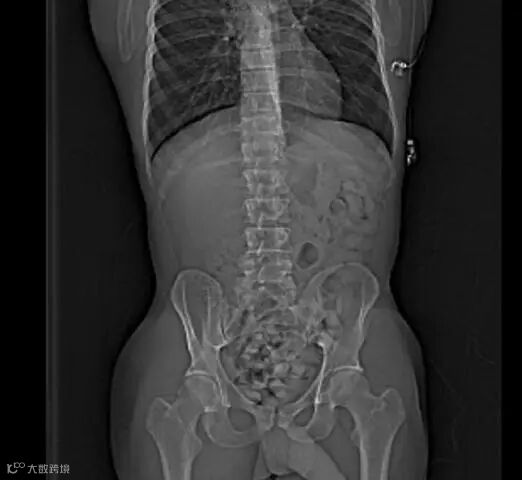

作为普通的放射科医生或技师,我们也可以在反诈、禁毒中尽自己的绵薄之力,尤其是看到这样图像时,请立即报警❗️❗️❗️

腹部CT扫描显示结肠(主要是降结肠、乙状结肠和直肠)有大量椭圆形高密度异物,这可不是“可爱的蚕宝宝”,而是小包分包的可卡因,大约有300-500g。